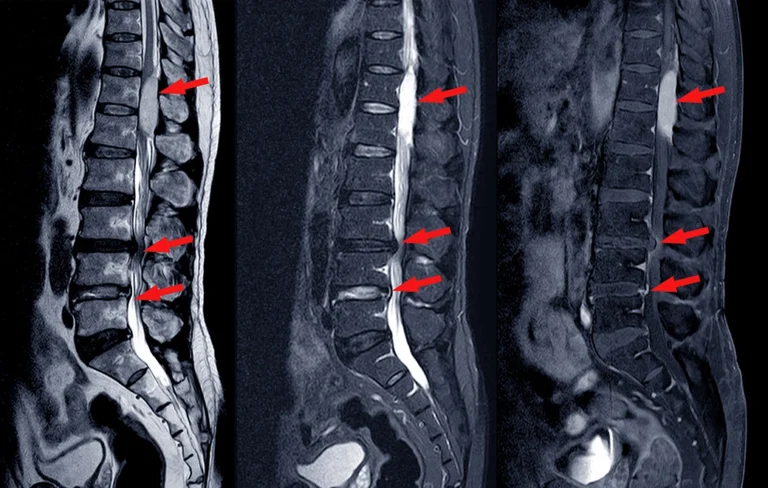

Have you been diagnosed with spinal stenosis? If so, don’t rush into surgery unless you have to. There are conservative treatments that may help. Your Anchorage chiropractor is here to…

If you are suffering from a bulging or herniated disc in the L5-S1 spinal level, there are specific exercises you should avoid. Below is a short list of such exercises…